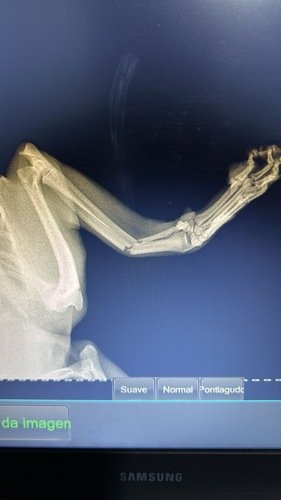

Oi, meu nome é Paçoca, não tenho 1 ano ainda e sou muito arteiro. Ontem quis fugir de dentro de casa pulando a janela, o que resultou na minha patinha quebrada, estou internado e preciso de cirurgia mas minha família não tem condições de pagar pois os custos são muito altos, por isso estou criando essa vakinha, se quiser ajudar, qualquer valor será bem vindo e ficarei muito grato. Estamos lhe encaminhando o orçamento solicitado:

👉🏽Consulta de Plantão:*R$ 220,00*👉🏽 Raio X:*R$ 220,00*👉🏽 Aluguel de bloco:*R$ 400,00*👉🏽 Internação:*R$ 60,00* x 4 = R$ 240,00👉🏽 Medicações pós procedimento: *R$ 70,00* x 4 = R$ 280,00👉🏽 Tratamento e medicações pós procedimento:*Á confirmar*